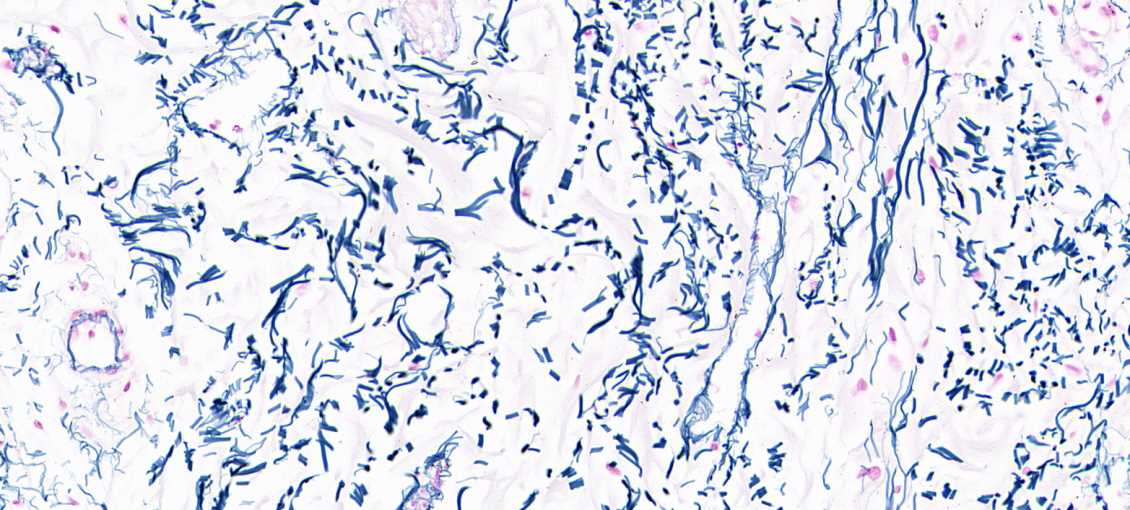

皮肤组织常见染色

基础染色:HE染色

特殊染色:甲苯胺蓝、天狼猩红、weigeirt、维多利亚蓝、MASSON等染色